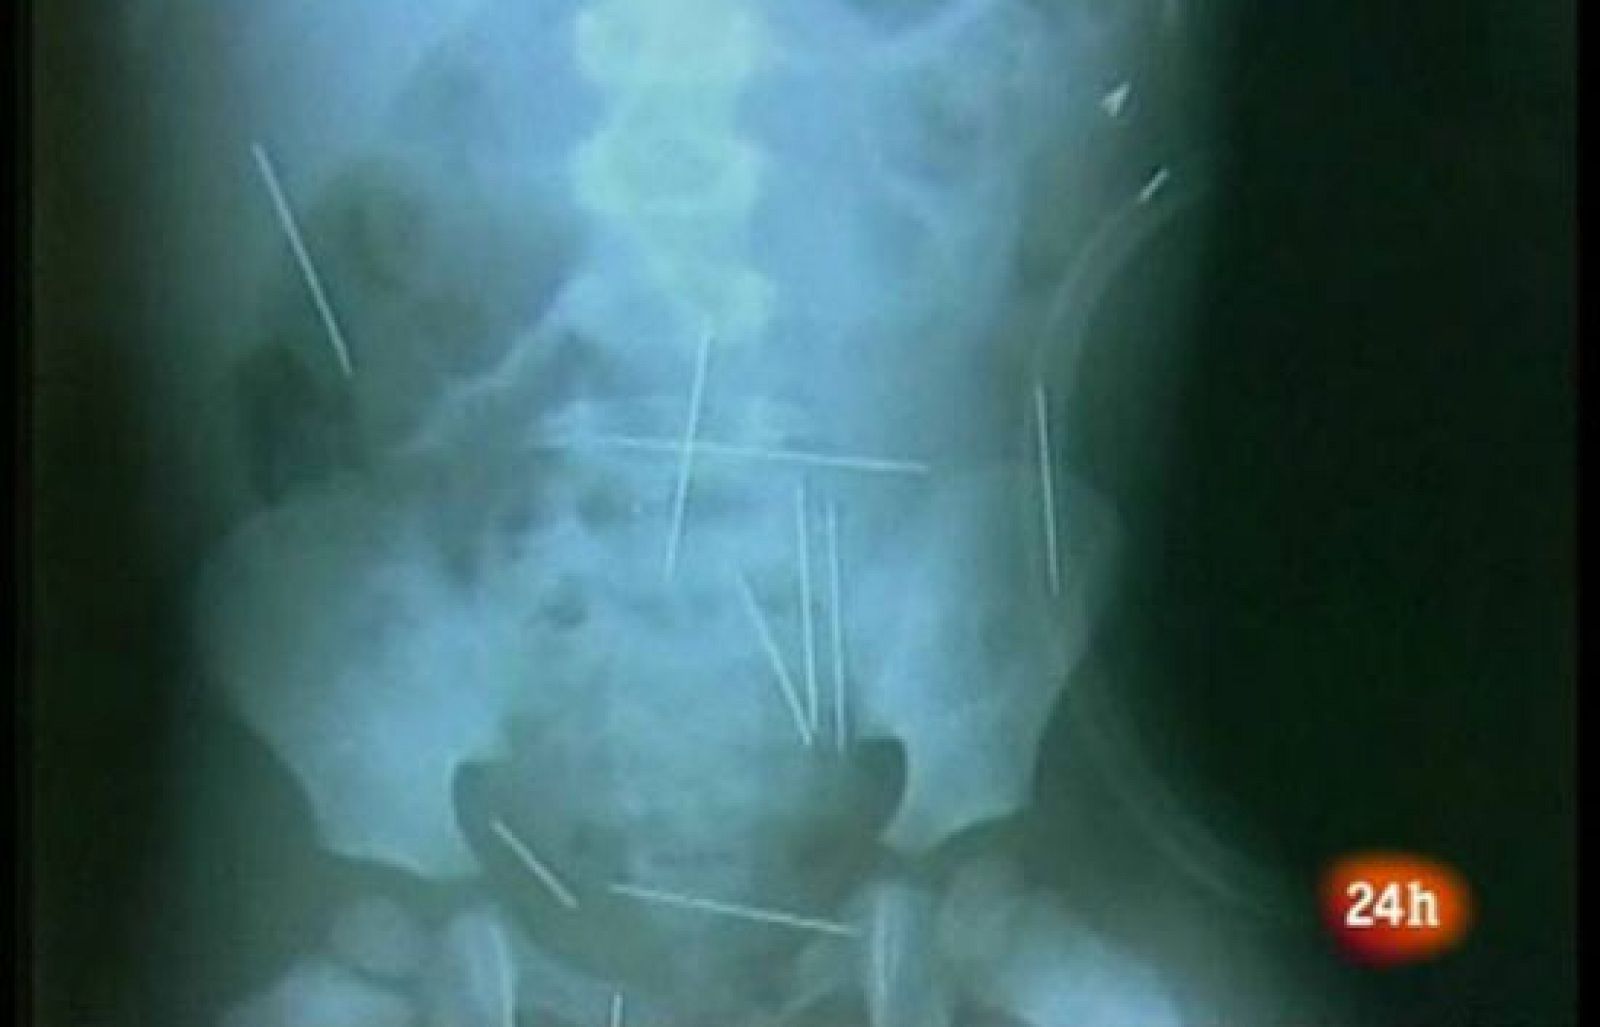

El brasileño Roberto Carlos Magalhães ha confesado haber aplicado 40 agujas a su hijastro, de dos años de edad, que está ingresado en estado grave en un hospital del estado de Bahía. El padrastro ha asegurado que llevó al niño varias veces a casa de una mujer llamada Angelina, donde clavó las 40 agujas con su colaboración y la de una tercera persona, cuyo nombre no ha sido divulgado. En su declaración, ha explicado que lo hizo a petición de Angelina, a quien le hizo caso porque estaba interesado sexualmente en ella. El niño permanece ingresado en un hospital y espera al inicio de la operación en la que se le van a extraer las agujas, que incluso le han perforado un pulmón. (17/12/09).